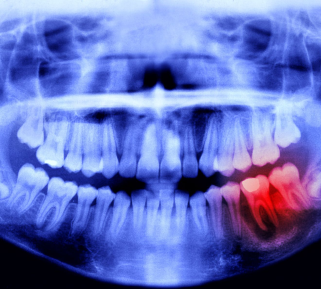

O exame radiográfico irá auxiliar, por exemplo, na localização de lesões cariosas não visíveis clinicamente, um outro exemplo é a lesão cariosa-câmara-pulpar, na localização de um traumatismo dentário, etc.

Os exames de radiografia são essenciais para se ter um bom diagnóstico, pois possibilitam a visualização de estruturas internas do corpo baseado nas diferenças de densidade entre elas.

No entanto, o médico só poderá fazer um diagnóstico preciso com uma alta qualidade da imagem radiográfica, ou seja, é preciso que ela apresente com nitidez a estrutura anatômica a ser analisada.